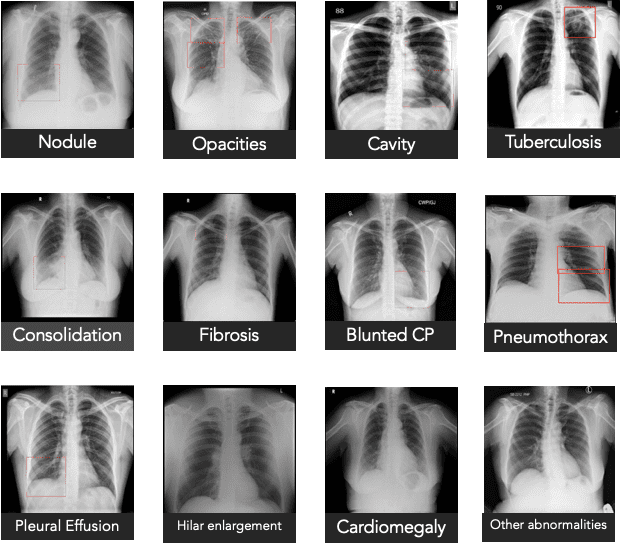

مصدر الصورة: كيور إيه آي

وعلى سبيل المثال، يستخدم نظام qXR من كيور إيه آي تركيبة من نماذج التعلم العميق لكشف الأنواع الشائعة من شذوذات الرئة. ولتعديله، عملت الشركة مع مجموعة من الخبراء لدراسة أحدث الأبحاث الطبية وتحديد الميزات النموذجية للالتهاب الرئوي الناتج عن كوفيد، مثل البقع البيضوية في الصورة، التي تتضمن نمطاً يشبه الزجاج المكسّر، إضافة إلى المناطق الكثيفة على جانبي الرئتين. قامت الشركة بعد ذلك بترميز هذه المعلومات ضمن qXR، وبهذا أصبحت الأداة قادرة على حساب احتمال الإصابة اعتماداً على عدد الصفات المميزة الموجودة في الصورة. وقد أجرت الشركة دراسة أولية للتحقق من صحة عمل النظام باستخدام 11,000 صورة للمرضى، ووجدت أن الأداة تمكنت من التمييز بين المرضى المصابين بكوفيد-19 وغير المصابين به بدقة 95%.